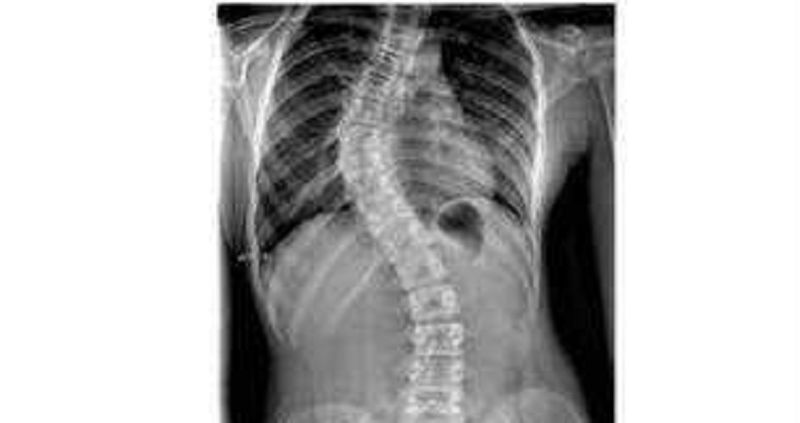

Welche Erkrankung beschreibt dieses Bild?

Skoliose

Spondylolisthese bei Spondylolyse

Morbus Scheuermann

Spondyloptose

Lasegue positiv

Adams test positiv

Adams test negativ

Peters test negativ